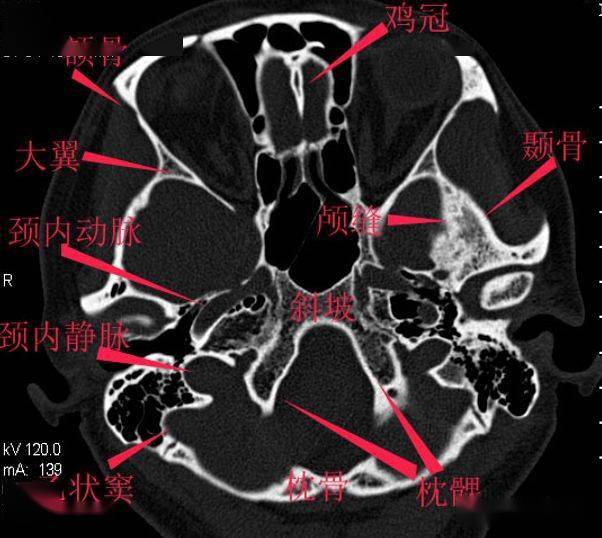

详细标注的颅底解剖

颅底ct